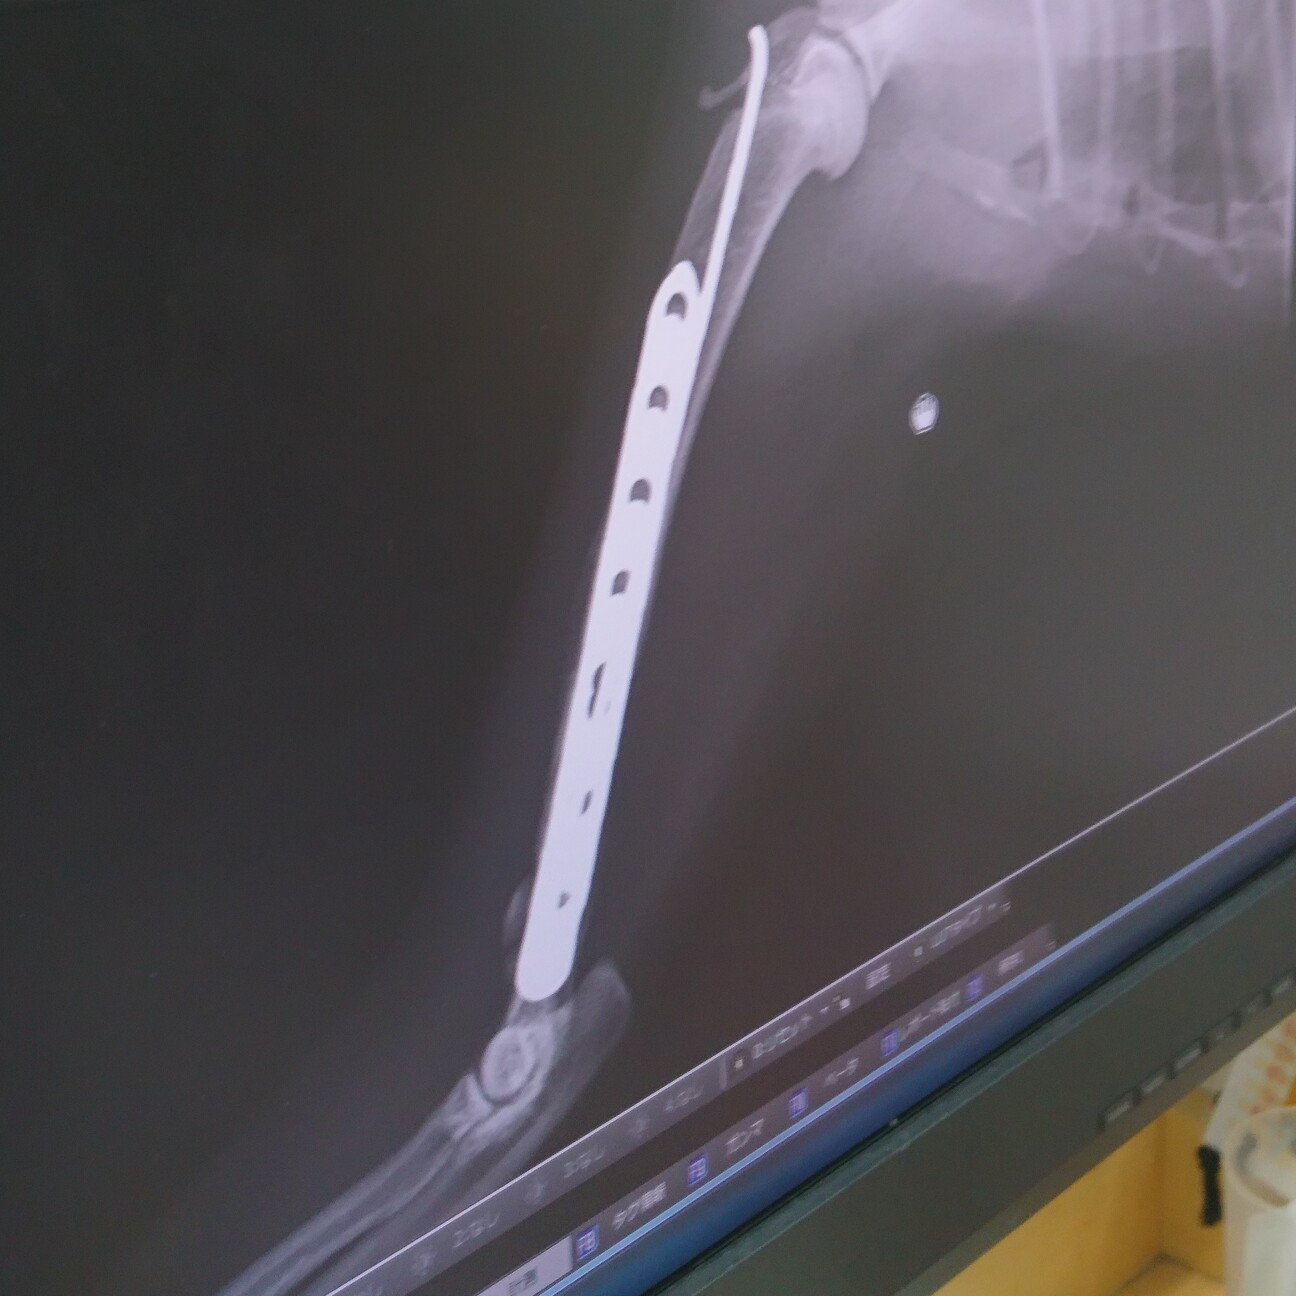

退院から1週間リハビリを耐えた雉白ちゃんの骨折はかなり良い状態に戻ってきました。

インプラントを右上腕骨に入れているため6月中は基本的にケージ内安静ですが、短時間ならジャンプをしないように目を離さず遊ばせてあげる許可が出たのでいっぱい遊んで血流を良くしたり刺激を与えてあげたいと思います。